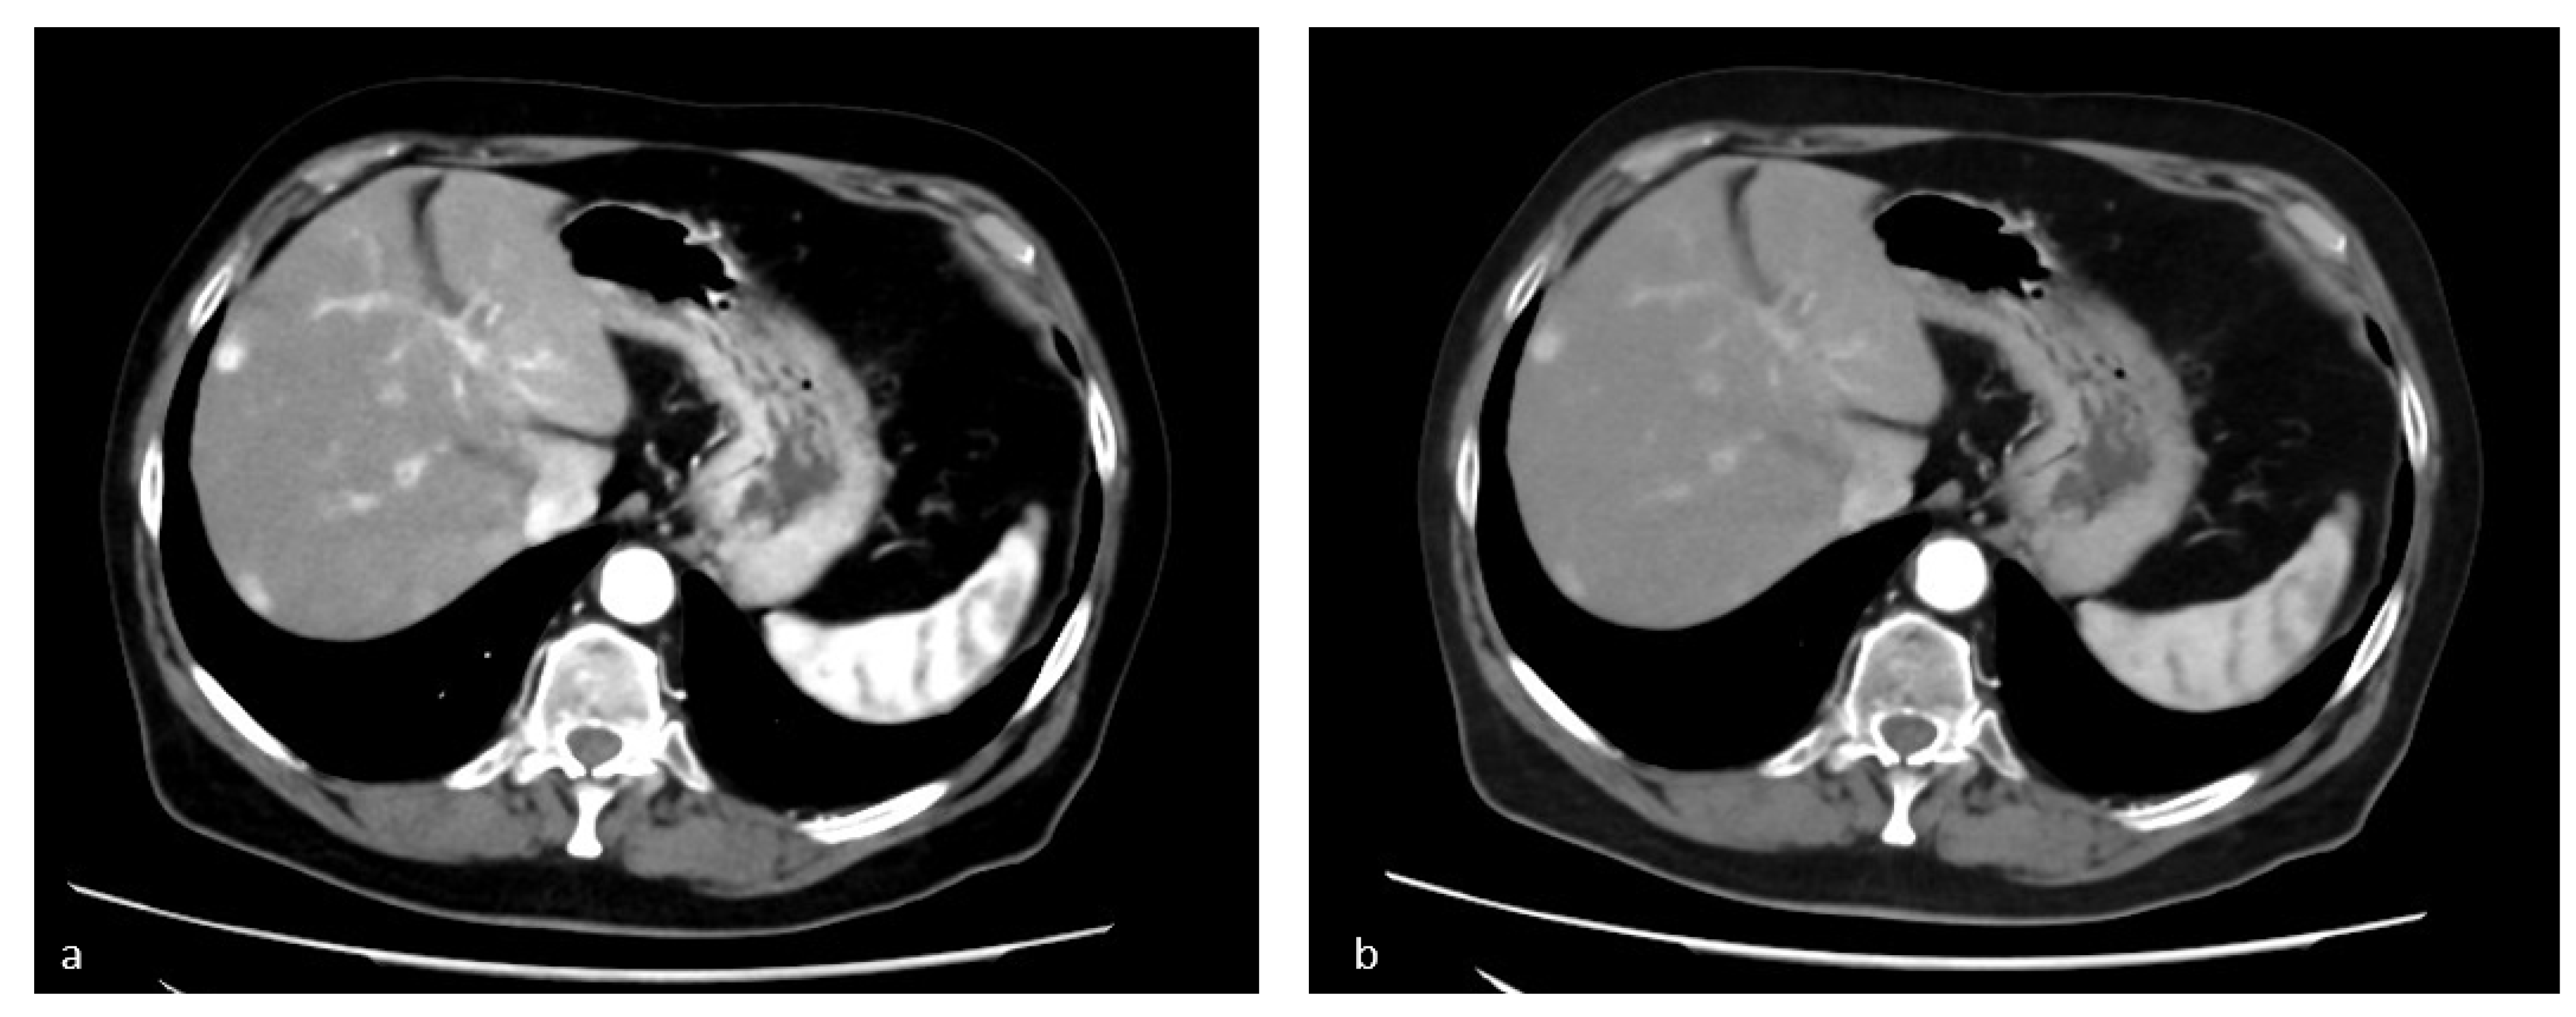

3.2. Virtual Non-Contrast Enhanced Image

- Graser, A.; Johnson, T.R.C.; Hecht, E.M.; Becker, C.R.; Leidecker, C.; Staehler, M.; Stief, C.G.; Hildebrandt, H.; Godoy, M.C.B.; Finn, M.E.; et al. Dual-Energy CT in Patients Suspected of Having Renal Masses: Can Virtual Nonenhanced Images Replace True Nonenhanced Images? Radiology 2009, 252, 433–440. [Google Scholar] [CrossRef]